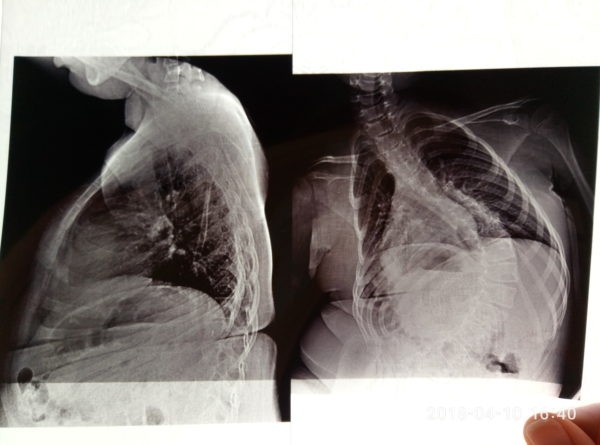

В этом году она перевела Полину на домашнее обучение. “Пятый класс, кабинетная система, 6-7 уроков, большая нагрузка, – объясняет она. – Но главное – прогрессирует заболевание”. На фоне мышечной атрофии у Полины развился сколиоз 4-й степени: сильно деформирован позвоночник, спинной мозг и внутренние органы. Нарушена работа сердца, сосудов, легких. Корсет, который Полина носит уже несколько лет, к сожалению, не может больше удерживать спину.

“Очень страшно наблюдать, как с каждым годом физические возможности твоего ребенка все хуже. В годик Полина еще умела ползать, в три – поднять руки выше головы. Сегодня дочка еле поднимает руку, чтобы почесать себе нос. Из-за сколиоза очень страдают внутренние органы, идет давление со стороны позвоночника на легкие, смещаются органы внутри таза. Девочка часто болеет, есть трудности с отхождением мокроты. От этого может возникнуть воспаление в дыхательных путях, развиться пневмония. От пневмонии часто и гибнут дети с таким заболеванием.

Остановить прогрессирование сколиоза возможно. Для этого необходимо установить стабилизирующую металлоконструкцию на кости позвоночника. Это вернет все органы в правильное положение, они не будут сдавлены, и Полина сможет нормально дышать и спать без боли.